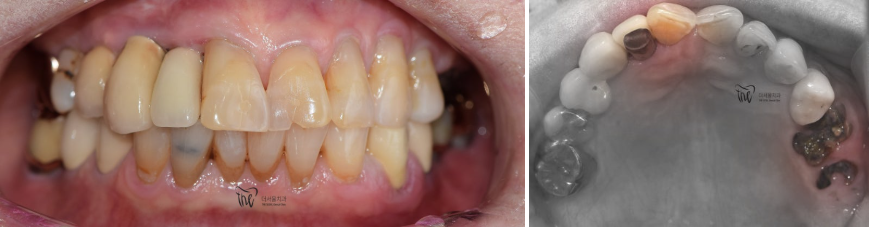

『증례 설명, 80세 환자』

구강 내 여러가지 문제점을 안고

더서울치과에 찾아오셨었습니다.

이미 연세도, 80세가 넘으셨기 때문에

구강 내 노화도 충분히 진행이 된 상태였습니다.

- 보철 하방 2차 우식증 발생

- 앞니 통증 호소 및 미세한 크랙, 우식증 발견

- 구치부 치관 소실 및 잔존 치근만 존재

이런 상황을 안고 오셨으며, 치과에 오실 때 부터

치아 통증을 호소하셨던 분입니다.

구강 내 사진을 보면, 이미 치은 퇴축이 상당히

진행 된 것을 볼 수 있으며 곳곳에 구강 위생 관리가

잘 되어있지 않은 것을 같이 볼 수 있었습니다.

다만 이 환자께선, 밝은 색의 크라운을

원하셨었습니다.

본래는, 양 옆에 있는 치아들과 색이 비슷하게

만들어 드려야 되는데 환자의 요청사항에 따라

화이트한 톤으로 만들어드렸습니다.